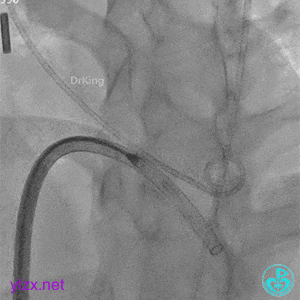

术中造影

结合实际术中造影,为大型膜部瘤室间隔缺损,左室入口直径12.79mm,右室出口直径为6.38mm,选择腰部直径为14的全降解封堵器进行封堵。